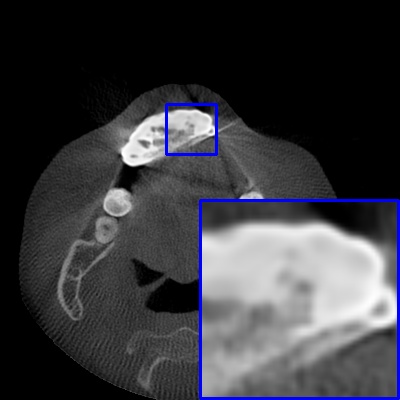

Figure 3: Visual comparison of MAR images by different methods on synthetic MA image. The PSNR (dB)/SSIM results are reported below each image for reference.

Results on synthetic MAR. In Table 1, we provide the quantitative results. One can see that our MARformer-L outperforms the other methods in terms of PSNR and SSIM, but needs only 11.76M parameters and 60.25G FLOPs. Note that the second best method Uformer-B has 50.42M parameters and 205.82G FLOPs. Besides, our MARformer-T achieves similar PSNR and SSIM results with Uformer-T, but needs only 0.40M parameters and 12.82G FLOPs compared to 5.24M and 25.39G for Uformer-T. Our MARformers also achieves faster inference speeds than the Uformers, though with inferior Dice scores, respectively. The qualitative results of visual quality are presented in Fig. 3. We observe that our MARformer-L well recovers the teeth shapes and obtains higher PSNR and SSIM results than the other comparison methods. The light-weight MARformer-L achieves similar results to Uformer-T. All these results validate that our MARformer is more efficient than the comparison methods on dental CBCT MAR.